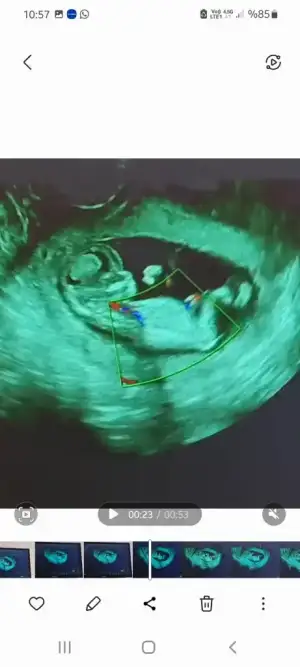

- 30 Eylül 2020

Benim geçen hafta aylık kontrole denk geldi zaten para vermiştim muayene 250 lira o yüzden daha 10 gün dolmadigi için şimdi vermedim sadece kana verdim 150 TL. Valla senin nerdeyse 1000 lirayı bulacakmis. Burda devlette de doktor mfk var görmüşsündür o var ama sıra bulunmuyormuş, bende 150 diyince uğraşmadim artıkBebişim 150 çok iyi bana burda 550 + muayene dediler devlete gittim bende aynı işlemi orda da yapıyorlar sonuçta sadece ilgisizlik oluyor iste